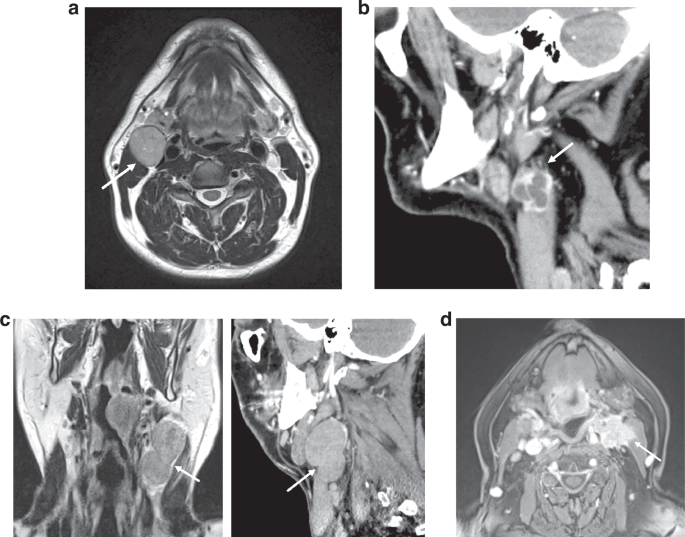

The 4-point scale used to score iENE [14, 15] is illustrated in the examples in Fig. 1a–d:

a Grade 0 iENE: Axial T2 MRI. Well-defined metastatic Level II node, clear perinodal fat (arrow). b Grade 1 iENE: Sagittal CECT. Metastatic Level II node with an irregular nodal margin + perinodal fat stranding (arrow). c Grade 2 iENE: Coronal T2 MRI + sagittal CECT demonstrating coalescence of metastatic Level II + III nodes (arrow). d Grade 3 iENE: Axial T1FS+c MRI demonstrating definite invasion of a metastatic Level II node into adjacent structures. Note the direct infiltration of sternocleidomastoid muscle (arrow)